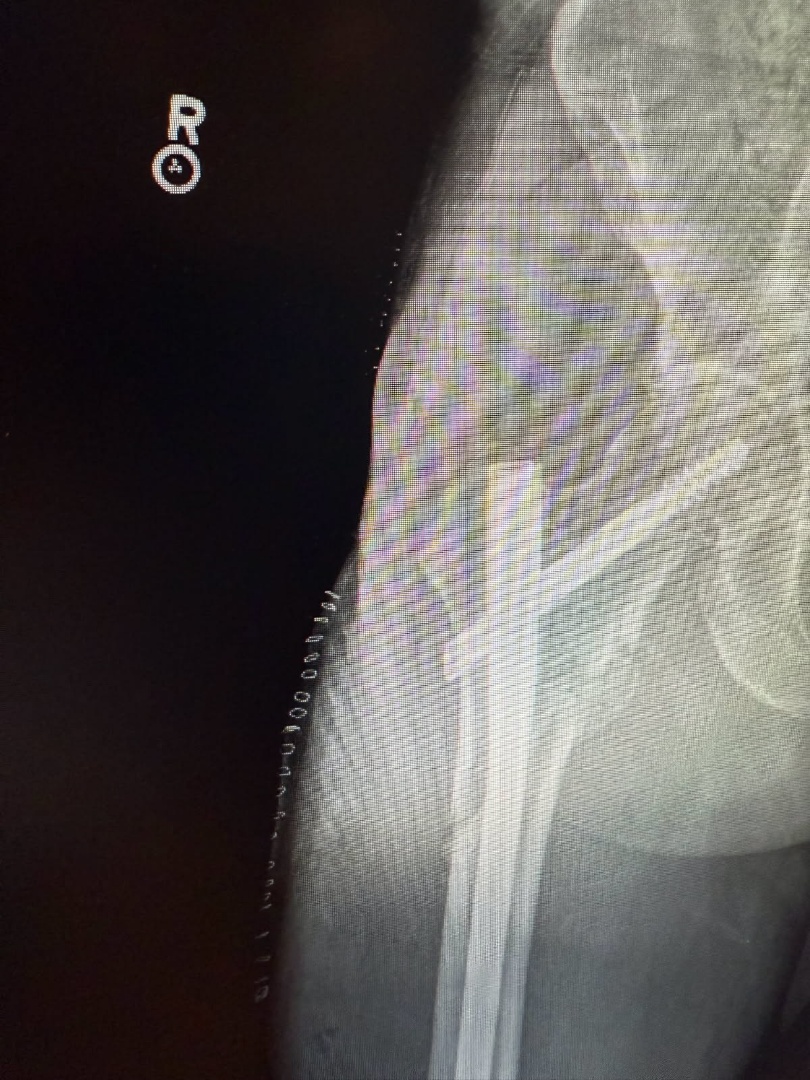

My brother-in-law… age 60 years, healthy, scuba diver - swimmer for a living… fell last night on the grass and broke his femur.

Makes me wonder what his bone density was before the fall. A pretty well-built man. Muscled… no fat.

He’s not the kind of guy that would check such a thing as bone density. So, probably not doing any bone density supplements. Now has a titanium rod.

A bit late…, but I suggested a DEXA bone scan. Good to know.